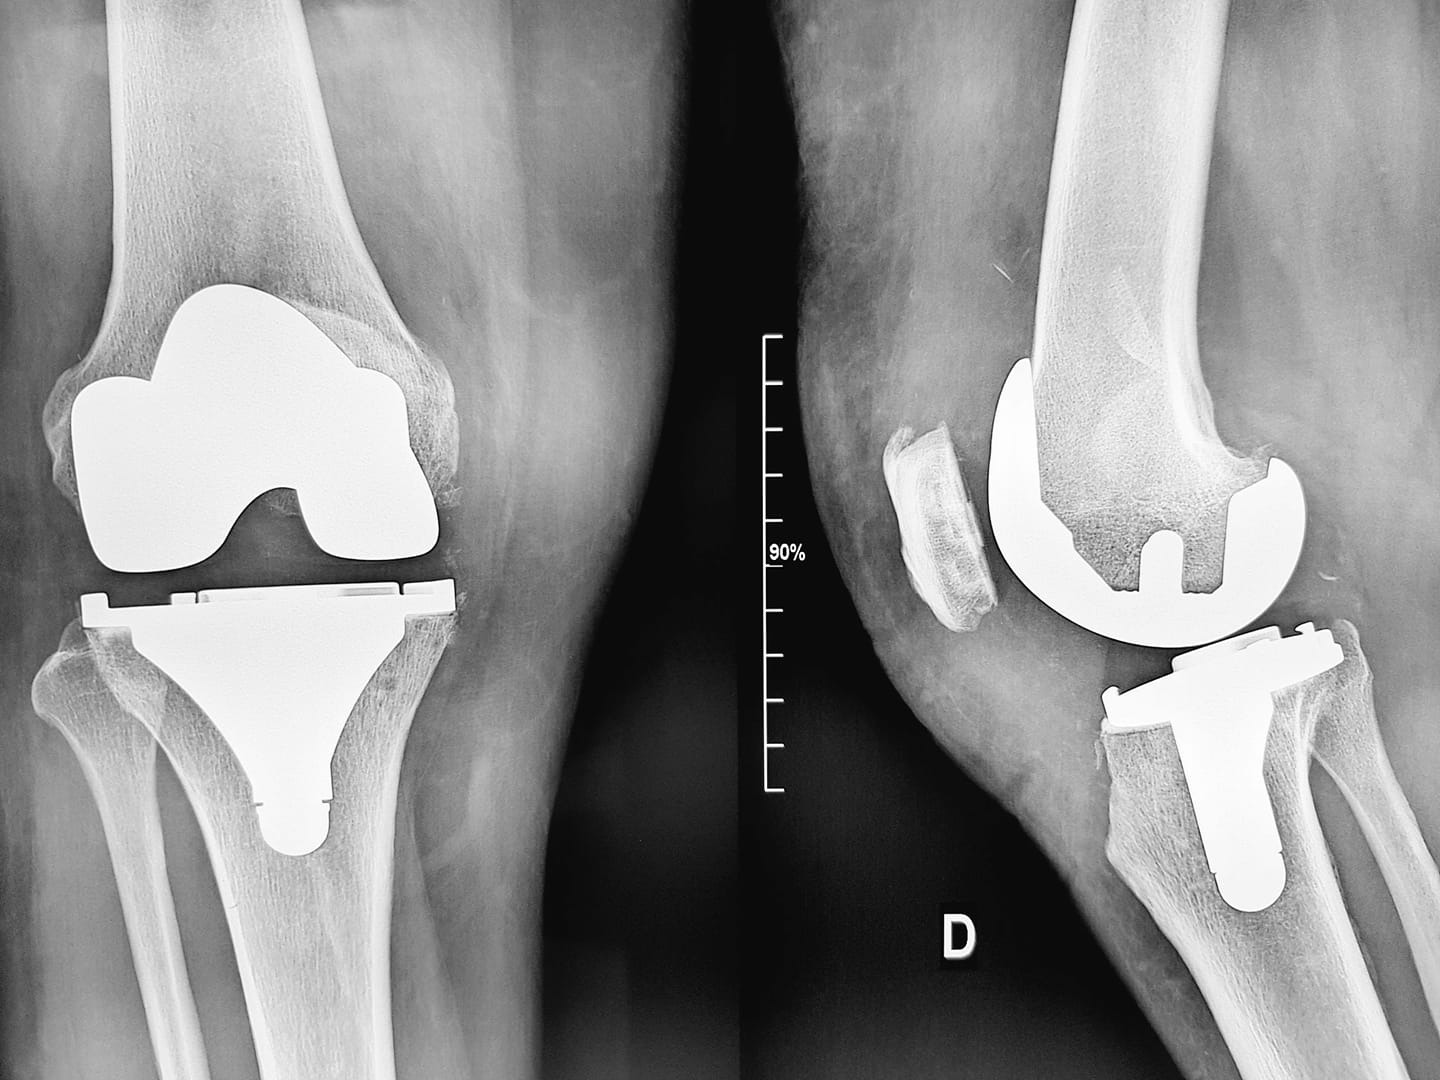

تعاني المريضة من تشوّه خلقي في مفصل الركبة، تسبب لها في آلام مزمنة وصعوبة كبيرة في الحركة، مما أثر سلبًا على جودة حياتها اليومية وقدرتها على القيام بأنشطتها الطبيعية.

بعد تشخيص حالتها بالتشوّه الخلقي النادر في مفصل الركبة، توجهت إلى مستشفى عائشة بنت حمد العطية، حيث خضعت لفحوصات دقيقة قبل أن يقرر الأطباء إجراء الجراحة المعقدة التي كانت بمثابة نقطة تحول في حياتها.

أجرى الفريق الطبي في مستشفى عائشة بنت حمد العطية جراحة معقدة تكللت بالنجاح، حيث تم تصحيح التشوّه وإعادة تأهيل الركبة لتستعيد المريضة قدرتها على المشي بشكل طبيعي، ودون ألم.